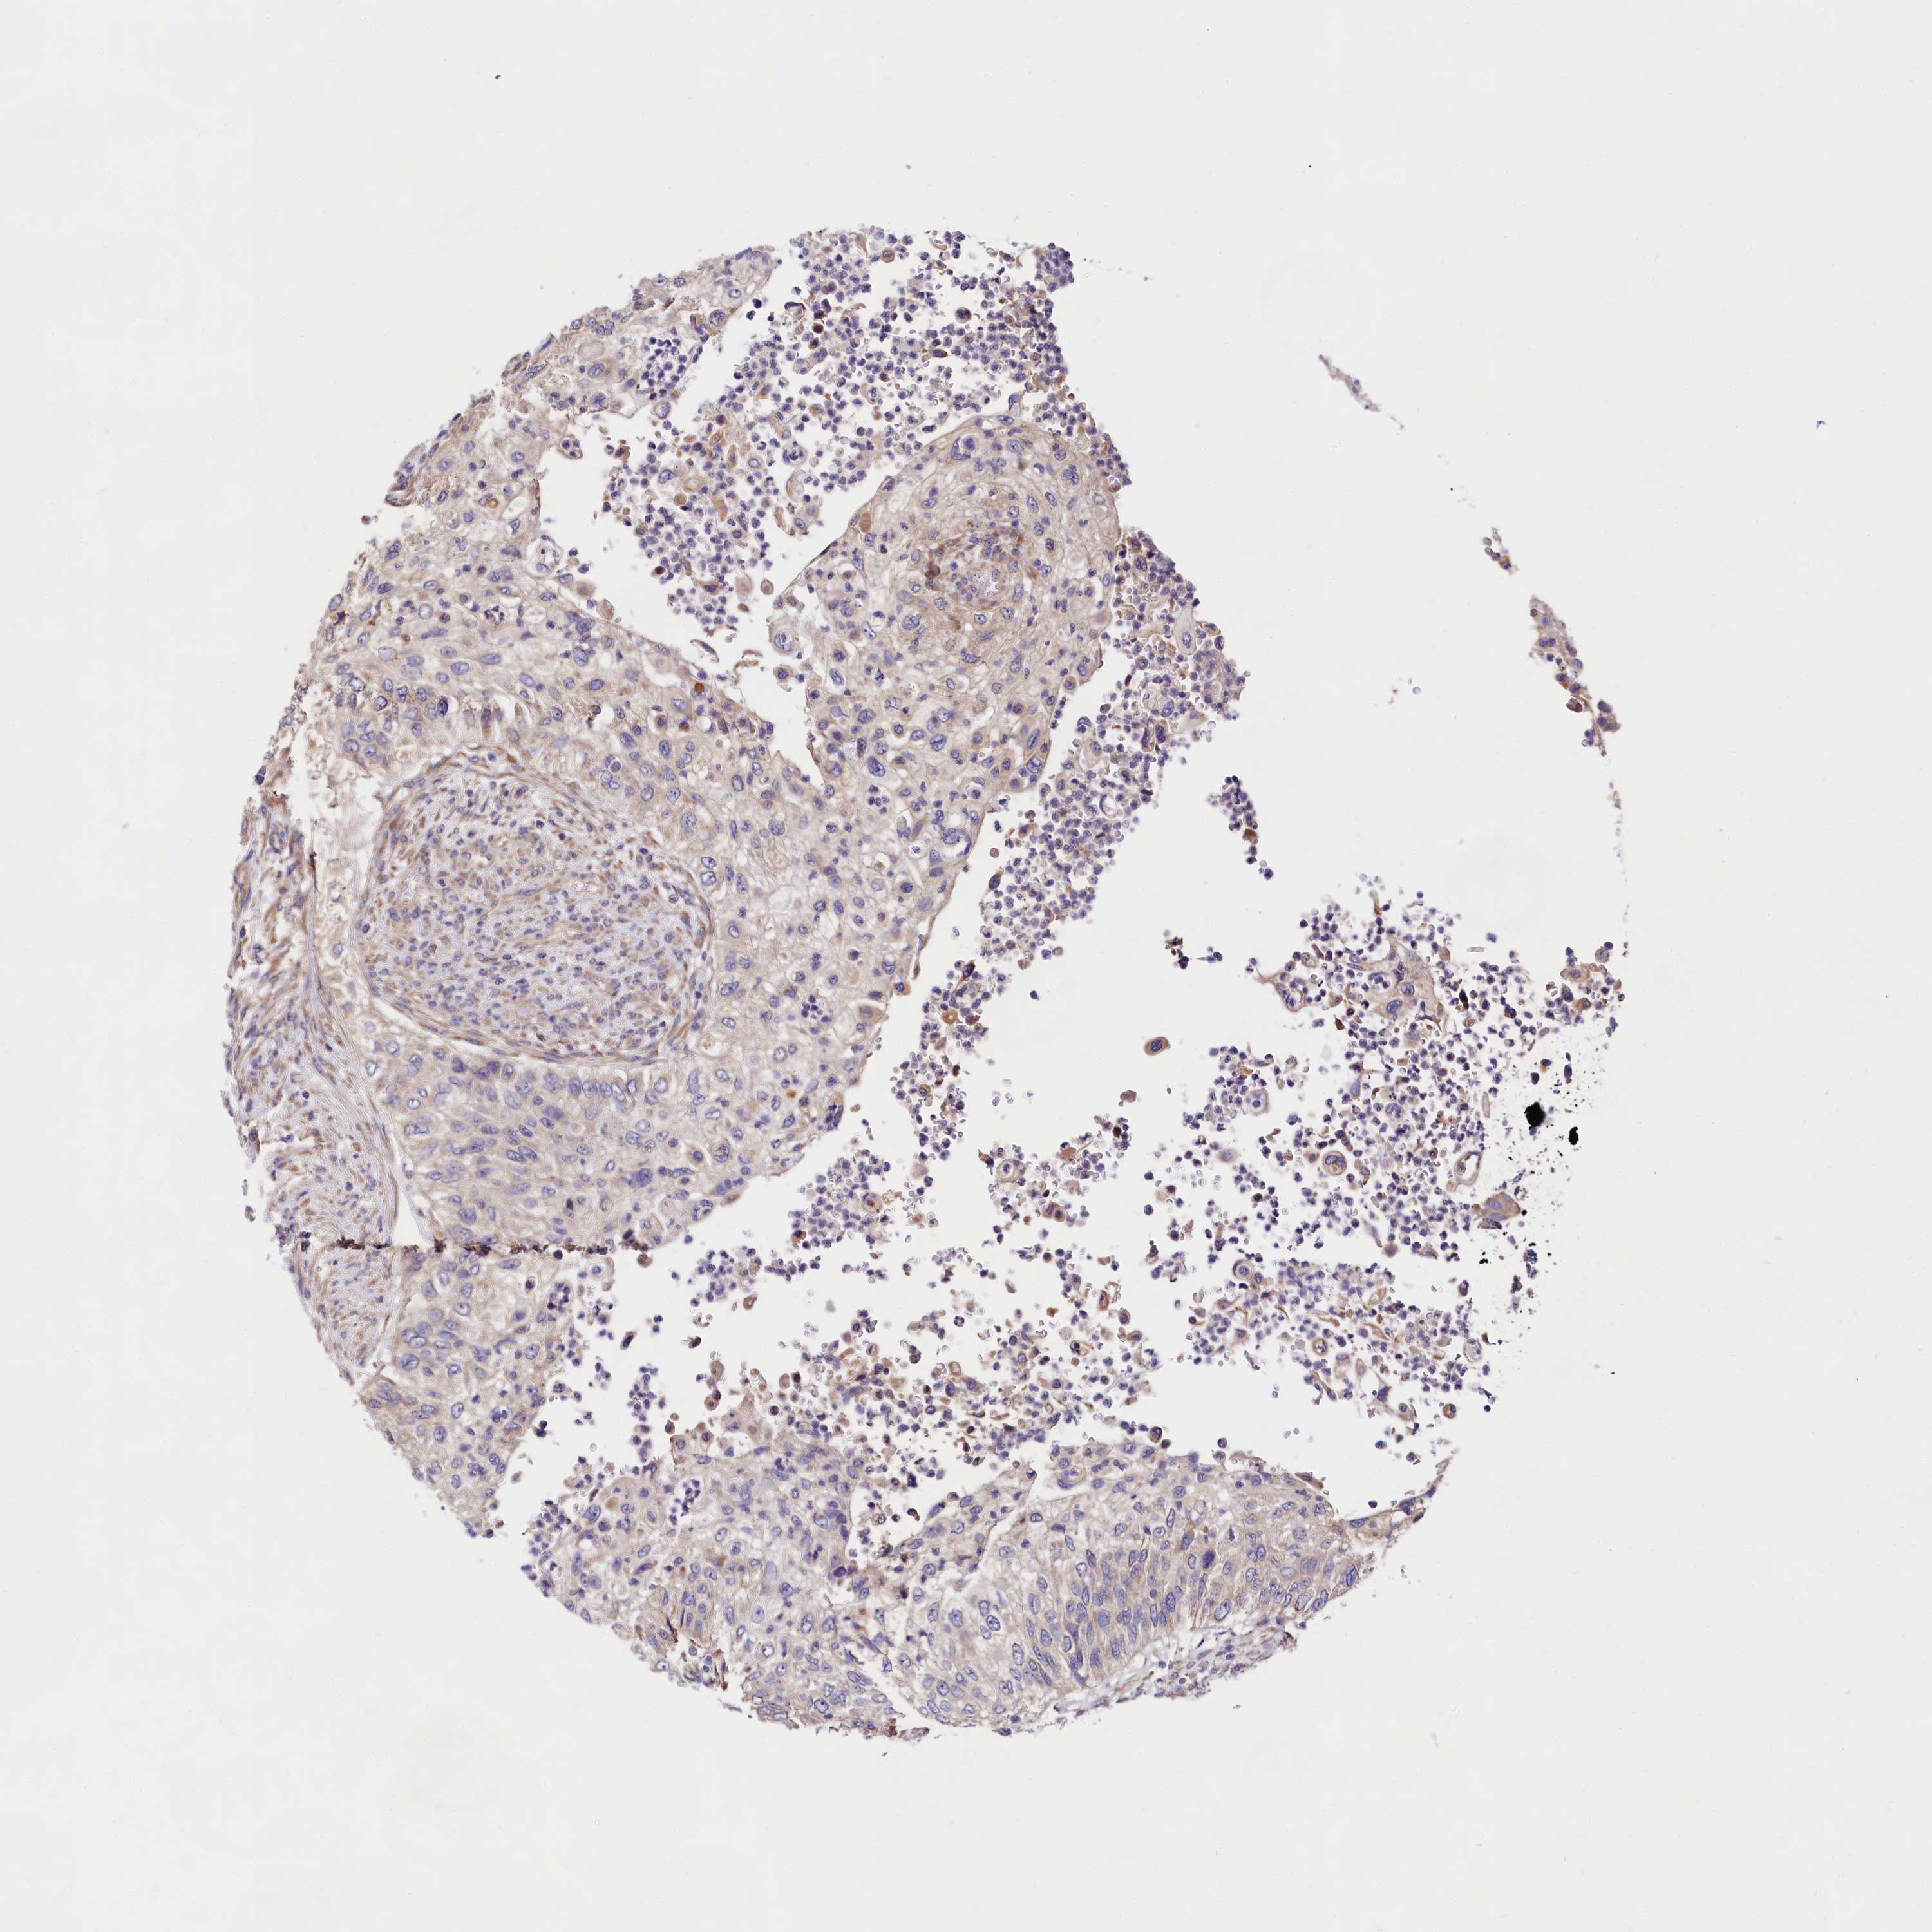

UROTHELIAL CANCER - Protein expressioni

A mouse-over function shows sample information and annotation data. Click on an image to view it in a full screen mode. Samples can be filtered based on level of antibody staining by selecting one or several of the following categories: high, medium, low and not detected. The assay and annotation is described here.

Antibody stainingi

Antibody staining in the annotated cell types in the current human tissue is reported as not detected, low, medium, or high, based on conventional immunohistochemistry profiling in selected tissues. This score is based on the combination of the staining intensity and fraction of stained cells.

Each image is clickable and will lead to virtual microscopy that enables deeper exploration of all samples and also displays staining intensity scores, fraction scores and subcellular localization as well as patient and tissue information for each sample.

Antibody HPA040412

Antibody HPA040947

Staining

High

Medium

Low

Not detected

Intensity

Strong

Moderate

Weak

Negative

Quantity

>75%

75%-25%

<25%

None

Location

Nuclear

Cytoplasmic/membranous

Cytoplasmic/membranous,nuclear

Urothelial carcinoma, Low grade